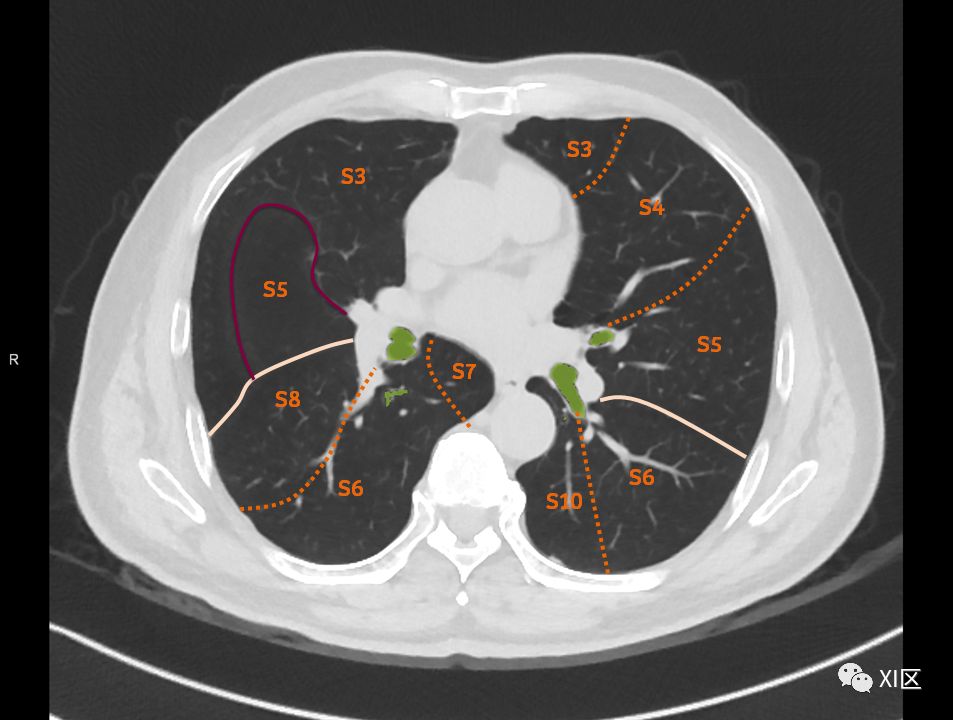

在进行肺的分段时,可以上下观察浏览,沿着相应气管的走形可以更容易准确地进行分段。

肺的分段

肺的断层分段示意图